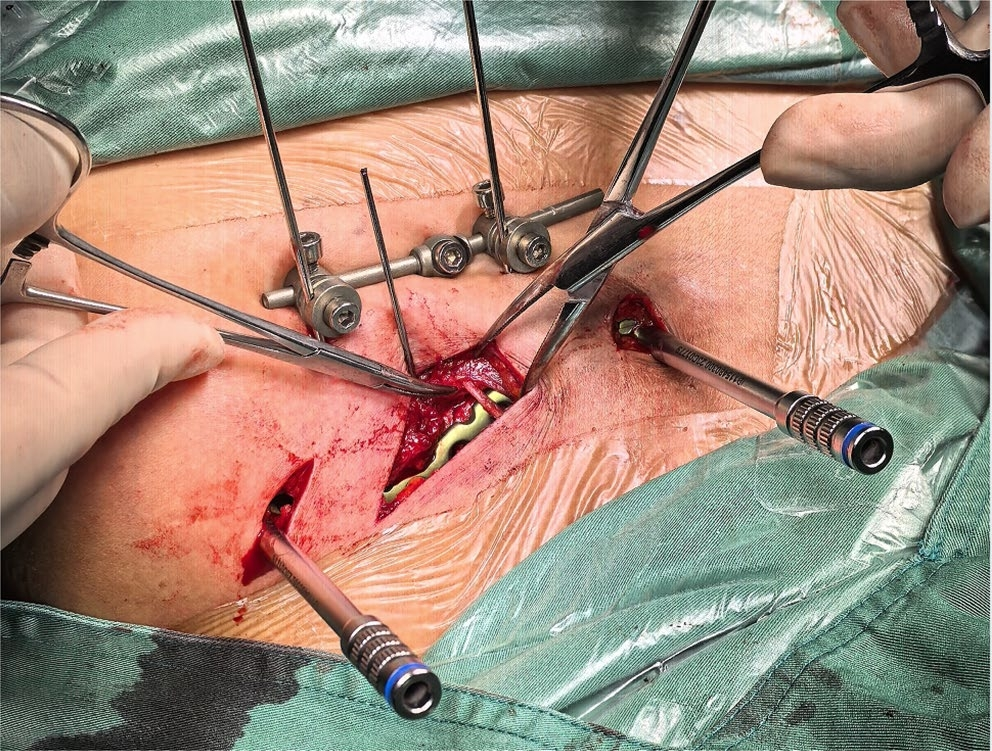

3、锁骨骨折显露图

4、锁骨骨折的复位和固定,推荐外固定器械辅助固定